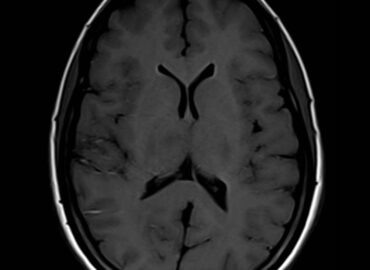

Masculino 40 años de edad HIV + Síndrome febril + pérdida de peso 18 Kg en los últimos 6 […]